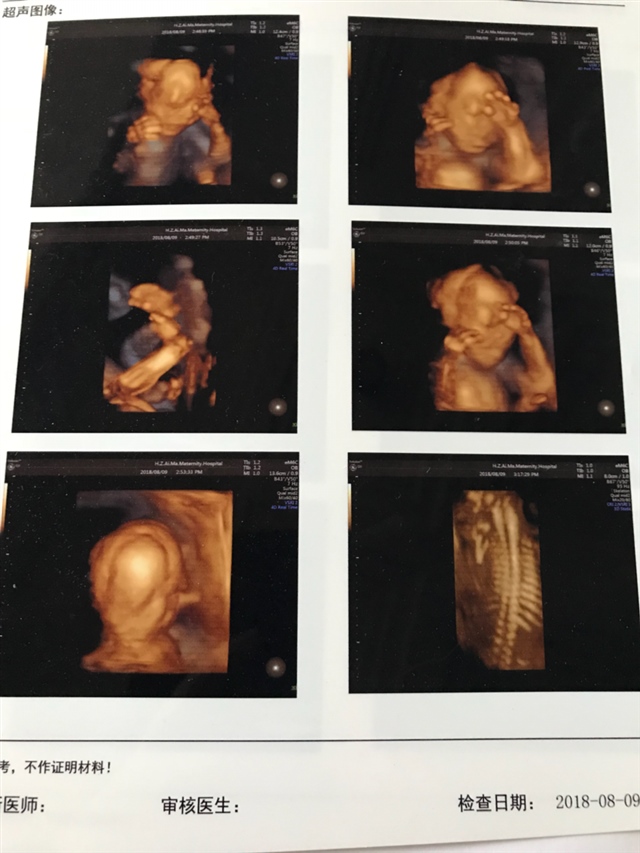

孕33周+6天